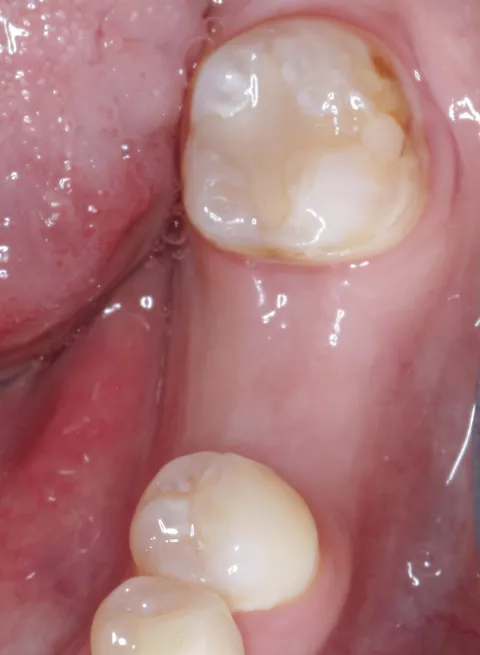

Unmittelbar im Anschluss an die OP erfolgte das Aufbringen eines Scan-Bodys (Straumann, CARES) mit digitaler Abformung der Implantatposition (Abb 14). Die Daten wurden unmittelbar über eine Cloud-Lösung auf den Arbeitsplatz des Zahntechnikers übertragen. Die Anfertigung der provisorischen Krone erfolgte durch Fräsen aus einem Kunststoffblock nach rein digitaler Planung (Abb. 15, 16; Labor Jörg Bies) in einem Zeitrahmen von zwei Stunden. Die provisorische Krone wurde direkt auf dem Implantat verschraubt (Abb. 17). Insbesondere wurde beim Einsetzen darauf geachtet, die periimplantäre Schleimhaut durch das Emergenzprofil der provisorischen Krone zu stützen. Die Okklusion wurde geprüft und die statische und dynamische Okklusion so weit reduziert, dass eine Interferenz durch Früh- und Störkontakte sicher ausgeschlossen werden konnte. Das postoperative Panoramaröntgenbild zeigt den korrekten Sitz von Implantat und Krone. Der Fadenzug erfolgte nach zehn Tagen bei sehr gut abgeheilten Wundverhältnissen.

Sechs Monate nach Implantation erfolgte die klinische und radiologische Kontrolle des Implantates. Bei solider Osseointegration und stabilen Schleimhautverhältnissen erfolgte daraufhin die Freigabe für die finale prothetische Versorgung des Implantates (Abb. 18).